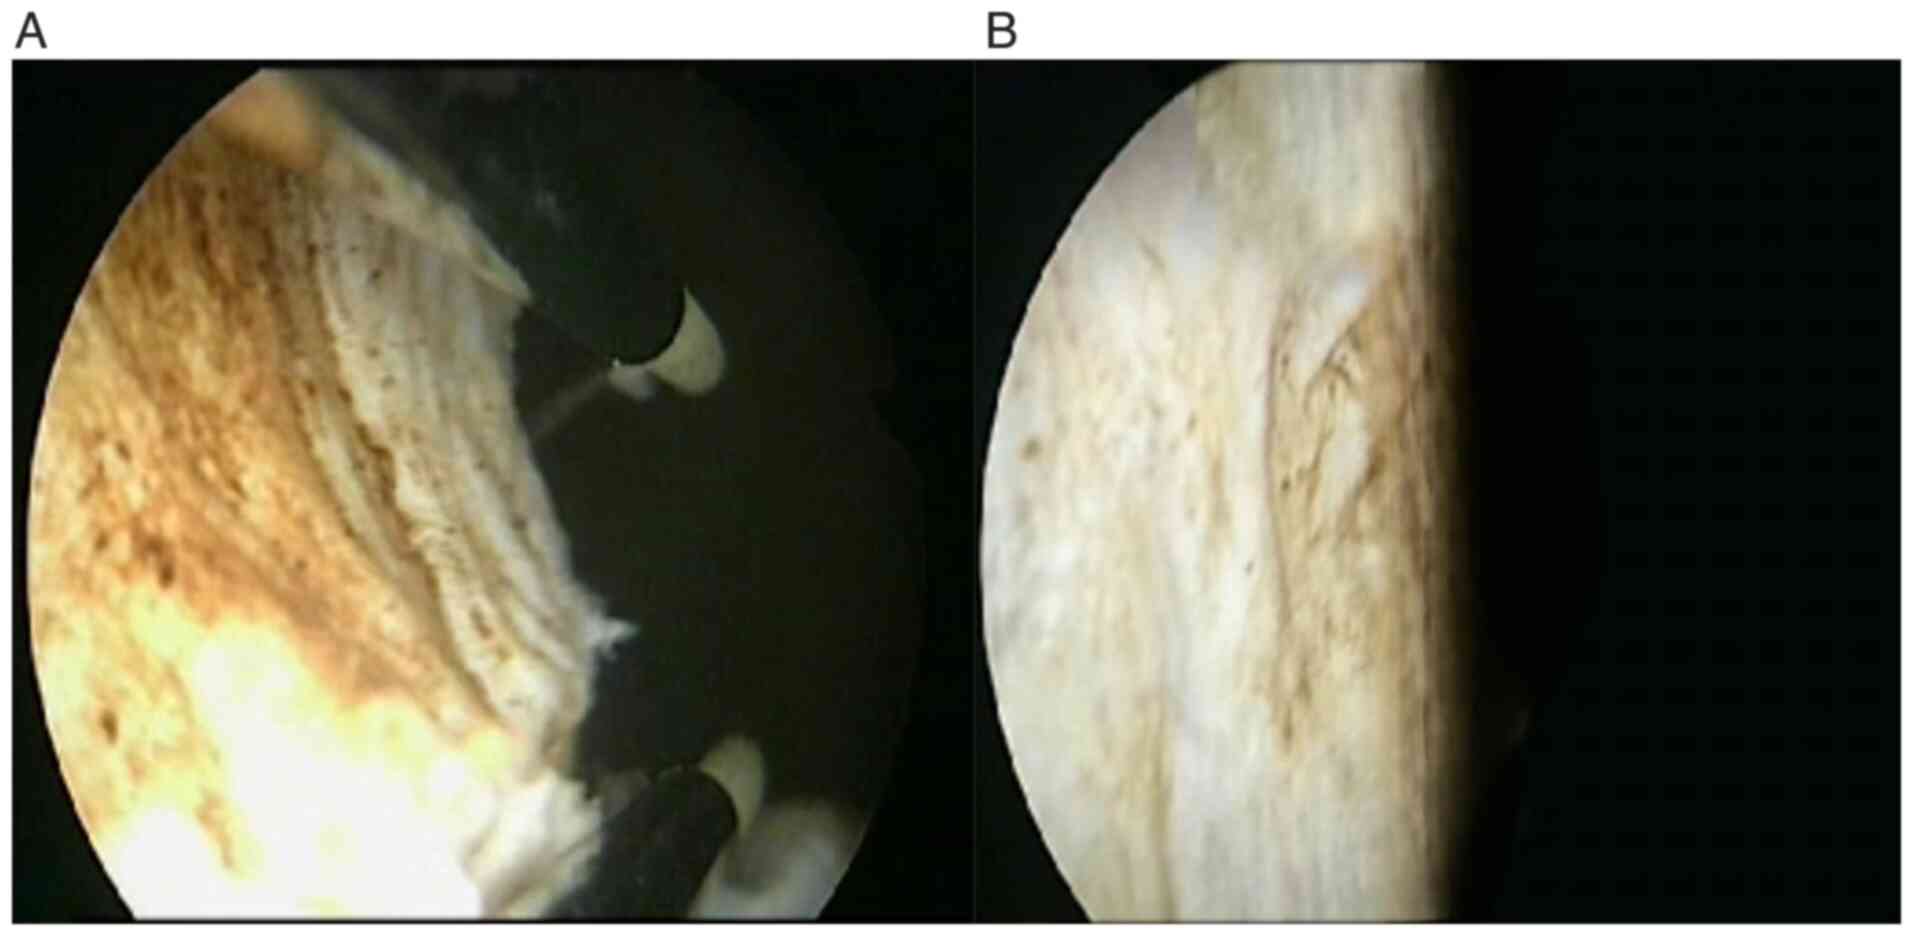

Bladder leiomyoma in the absence of symptoms: A case report and mini‑review of the literature

Figure 3